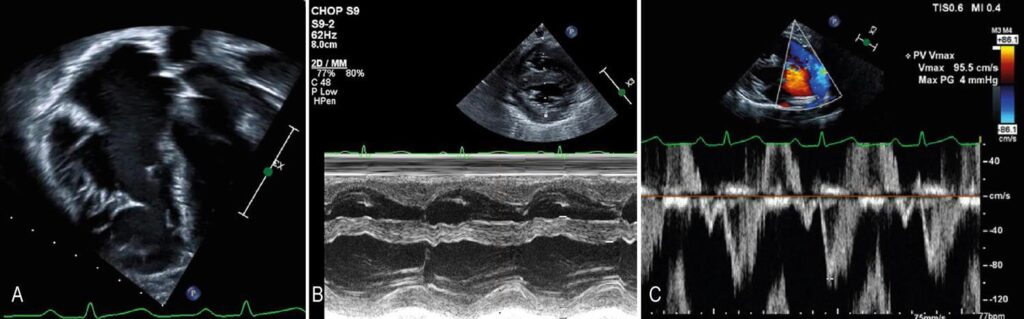

No corte apical de quatro câmaras, eu examino o movimento da valva tricúspide em direção ao ápice (medido como a excursão sistólica do plano anular tricúspide — ou TAPSE — detalhado abaixo) e o movimento da parede VD em direção ao septo, sempre comparando com estudos anteriores. Os cortes paraesternais nos eixos longo e curto também são importantes. Naqueles com janelas acústicas favoráveis, o encurtamento da parede VD também pode ser avaliado pelo modo-M. ( ) É importante ressaltar que a avaliação qualitativa da função VD não deve ser usada como único parâmetro para avaliar a função VD. ,